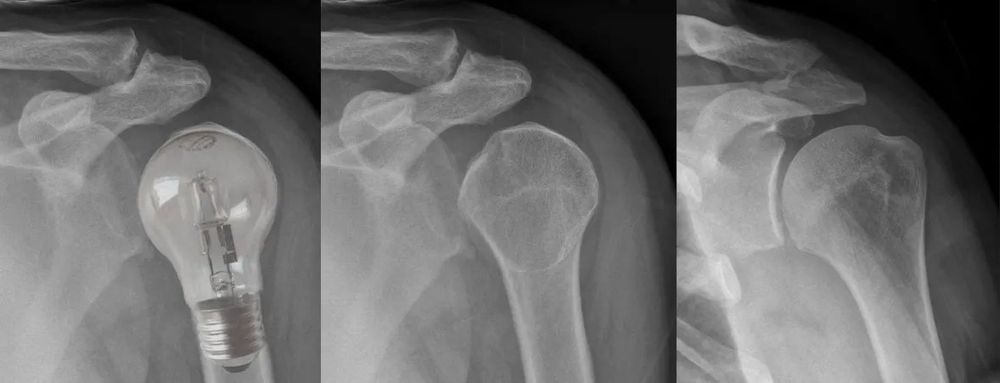

13/

๐งพ Scans and Stories

In older shoulders, imaging finds something in almost everyone.

Pain-free rotator cuff tears, โbursitisโ in half the population, OA in most.

Use scans to confirm your theoryโnot to build it.